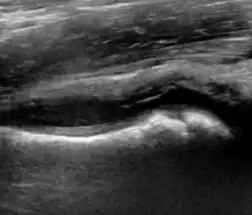

During childhood, ultrasound is a quick method to assess hip pain and quite often may be used to avoid use of irradiating techniques, such as radiography or CT. Ultrasound allows evaluation of joint effusion, synovial thickening and neovascularity, the bone/cartilage contour, and the femoral head-neck alignment. Although sonography is extremely sensitive in detecting increased synovial fluid, it is nonspecific and cannot be used with accuracy to determine the type of fluid. Transient synovitis of the hip, despite being the most frequent cause of pain in children between 3 and 10 years, remains a diagnosis of exclusion. It usually shows anechoic fluid, but echogenic fluid can also be found. The effusion is considered pathologic when it is measured at >2 mm in thickness. The differential diagnosis is wide, including osteomyelitis, septic arthritis, primary or metastatic lesions, LCPD, and SCFE. Discrimination from septic arthritis is challenging, often requiring joint aspiration. In septic arthritis, US is able to demonstrate a hip joint effusion, synovial thickening, and cartilage damage, although the appearances are nonspecific.[1]

A step between the head and the physis can be detected in children with SCFE, while abnormalities in the femoral head contour may suggest the presence of LCPD. In both cases, radiographs are mandatory to confirm diagnosis and severity (Figure 12).[1]

Figure 12:

Joint effusion in transient synovitis of the hip. -